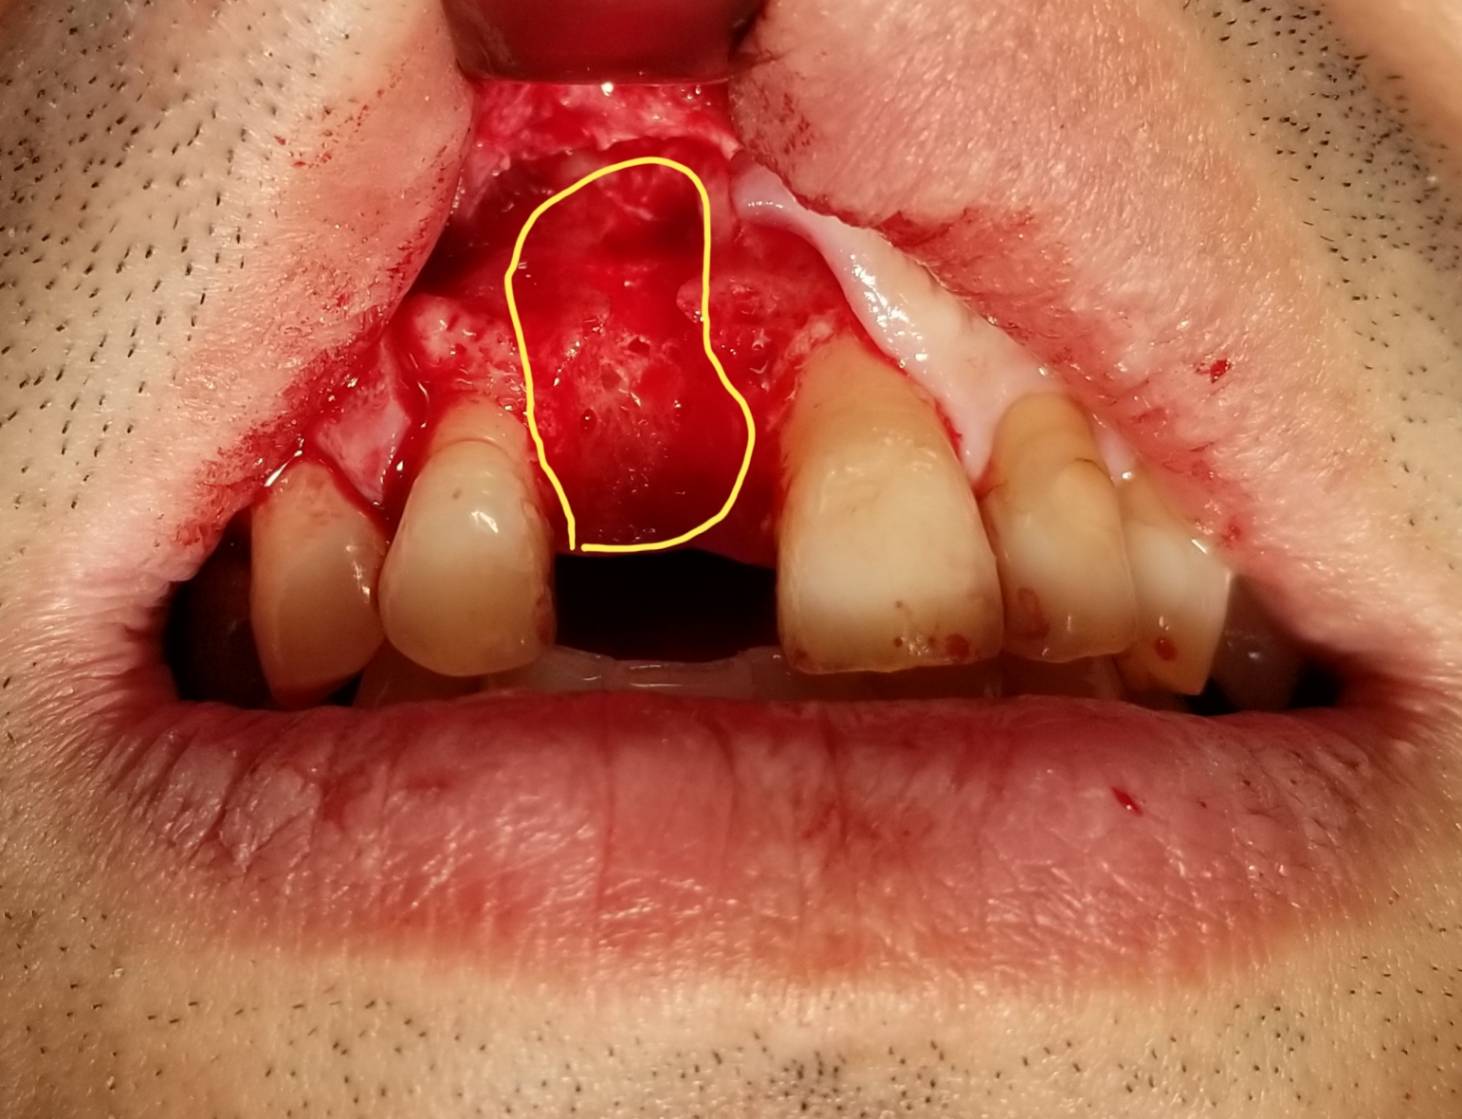

抜歯後は抜いた穴から掃除をしていきましたが、根の先に病巣があり、それが頬側の骨を吸収しており、さらに頬側の粘膜にくっついていたため、歯茎を一部切開して病巣を取り除きました。

写真に示します(黄色囲い部分)